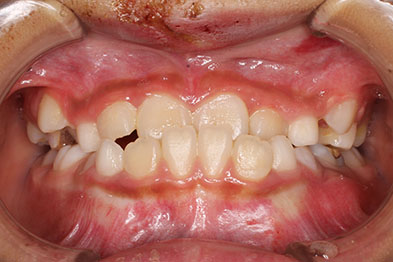

| 前歯の生え変わりの時期(小学校低学年)、受け口が気になるということで相談に来られた患者さんです。 上の前歯が内側(舌側)にあり、受け口のかみ合わせです。 上顎前歯部は、生え変わりのスペース不足により、八重歯になりやすい状態でした。 小児矯正では、上の前歯を前方に拡大し、がたつきの緩和と被蓋改善まで治療を行い、その後、下顎の成長を経過観察。 下顎の前方成長による受け口のかみ合わせは再発しませんでしたので安心しましたが、 上顎第二大臼歯(上の後ろの歯)が萌出スペース不足により、頬側(外側)に飛び出して生えてきました。 本格矯正では、その第二大臼歯のかみ合わせを改善するために、小臼歯抜歯を行い本格矯正を開始。第二大臼歯を正常な位置に移動させ終了ました。 マルチブラケット 動的治療期間 2年5か月 調整回数17回 来院間隔は、1~3か月に1回ペースでした。